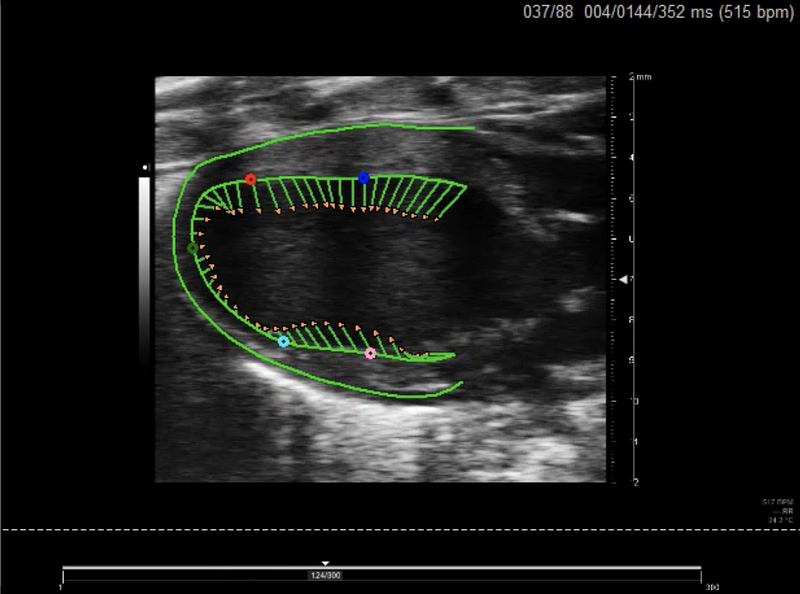

A new framework for performing cardiac strain analysis from cine MRI imaging in mice

K Hammouda, F Khalifa, H Abdeltawab, A Elnakib, G A Giridharan, M Zhu, C K Ng, S Dassanayaka, M Kong, H E Darwish, T M A Mohamed, S P Jones, A El-Baz

Sci. Rep., vol. 10, 2020 May, p. 7725